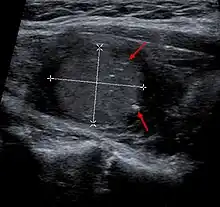

Medullary thyroid carcinoma may also produce a thyroid nodule and enlarged cervical lymph nodes.[4]